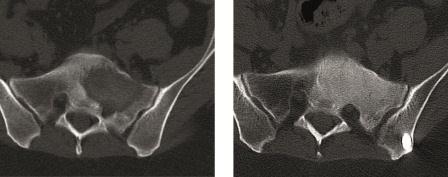

Sakrummetastasen: Stabilitätsgefährdende Metastasen am Sakrum (Abb. 3a) und am hinteren Beckenring werden zumeist mit einer mono- oder bilateralen vertebropelvinen Abstützung versorgt (Abb. 3b). Insbesondere das Os sacrum kann so aus der lasttragenden Kette herausgenommen werden. Vor allem bei Mammakarzinommetastasen kann mit der nachfolgenden Radiatio häufig eine so stabile Rekalzifikation erzielt werden (Abb. 3c), dass mitunter bei Beschwerden über dem Fixateur besonders bei schlanken Patienten eine Metallentfernung erwogen werden kann. Sollte das dorsale Os ileum mit betroffen sein (Abb. 4a) kann bei entsprechenden anatomischen Voraussetzung (Abb. 4b) auch weiter ventral auf den Beckenkamm abgestützt werden (Abb. 4c).